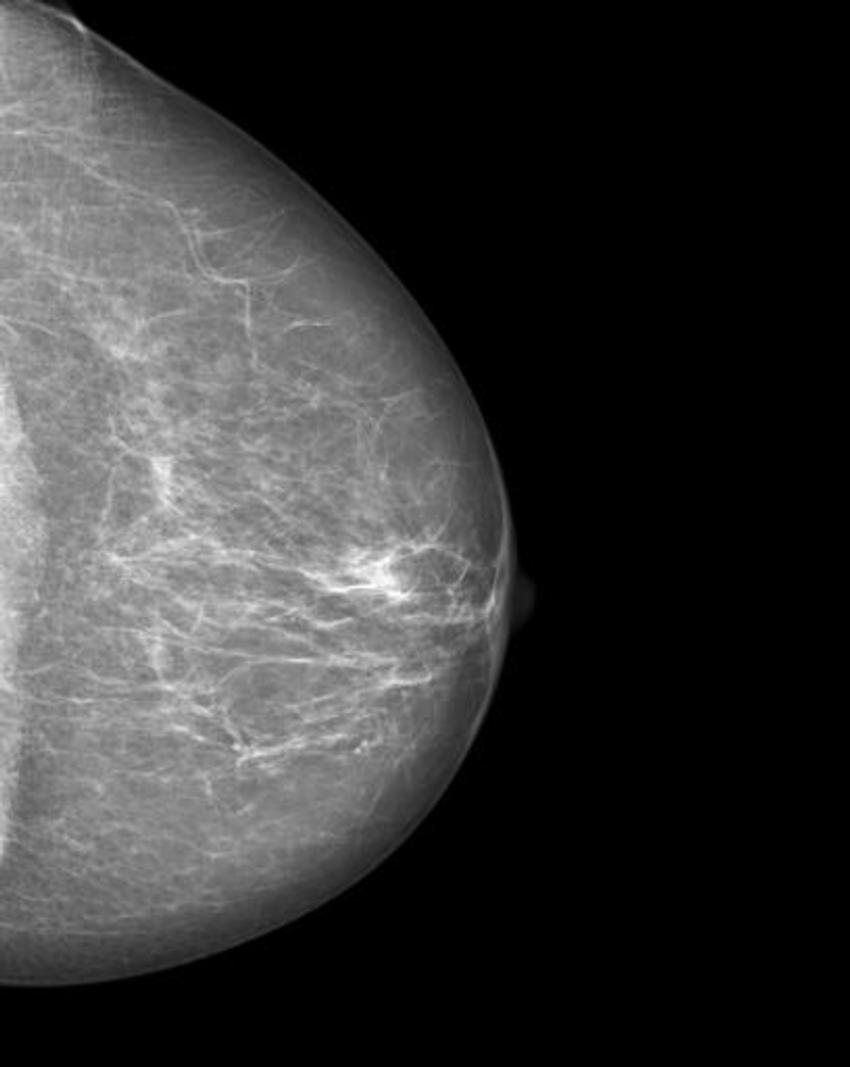

The researchers trained a cycle-consistent generative adversarial network (CycleGAN), a type of artificial intelligence application, on 680 mammographic images from 334 patients, to convert images showing cancer to healthy ones and to do the same, in reverse, for the normal control images. They wanted to determine if a CycleGAN could insert or remove cancer-specific features into mammograms in a realistic fashion.

The images were presented to three radiologists, who reviewed the images and indicated whether they thought the images were genuine or modified. None of the radiologists could reliably distinguish between the two.

"Neural networks, such as CycleGAN, are not only able to learn what breast cancer looks like," Dr. Becker said, "we have now shown that they can insert these learned characteristics into mammograms of healthy patients or remove cancerous lesions from the image and replace them with normal looking tissue."

Figure 2. Manipulated mammogram of breast in Figure 1 with a neural-network-generated mass.

High-res (TIF) version